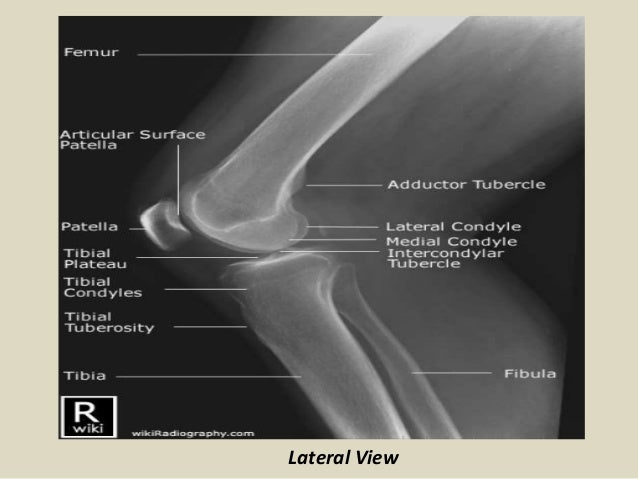

Knee normal ap. Anteroposterior and lateral views of the knee are most common knee x rays done.

Knee xray anatomy. Normal radiographic anatomy of the knee. The patellar tendon goes from the inferior pole of the patella to the tibial tuberosity. Knee x rays are done to assess the knee joint pathology.

This allows effusions to be visualised in the suprapatellar pouch. Use the mouse to scroll. The knee joint is a modified hinge joint between the femur tibia and patella.